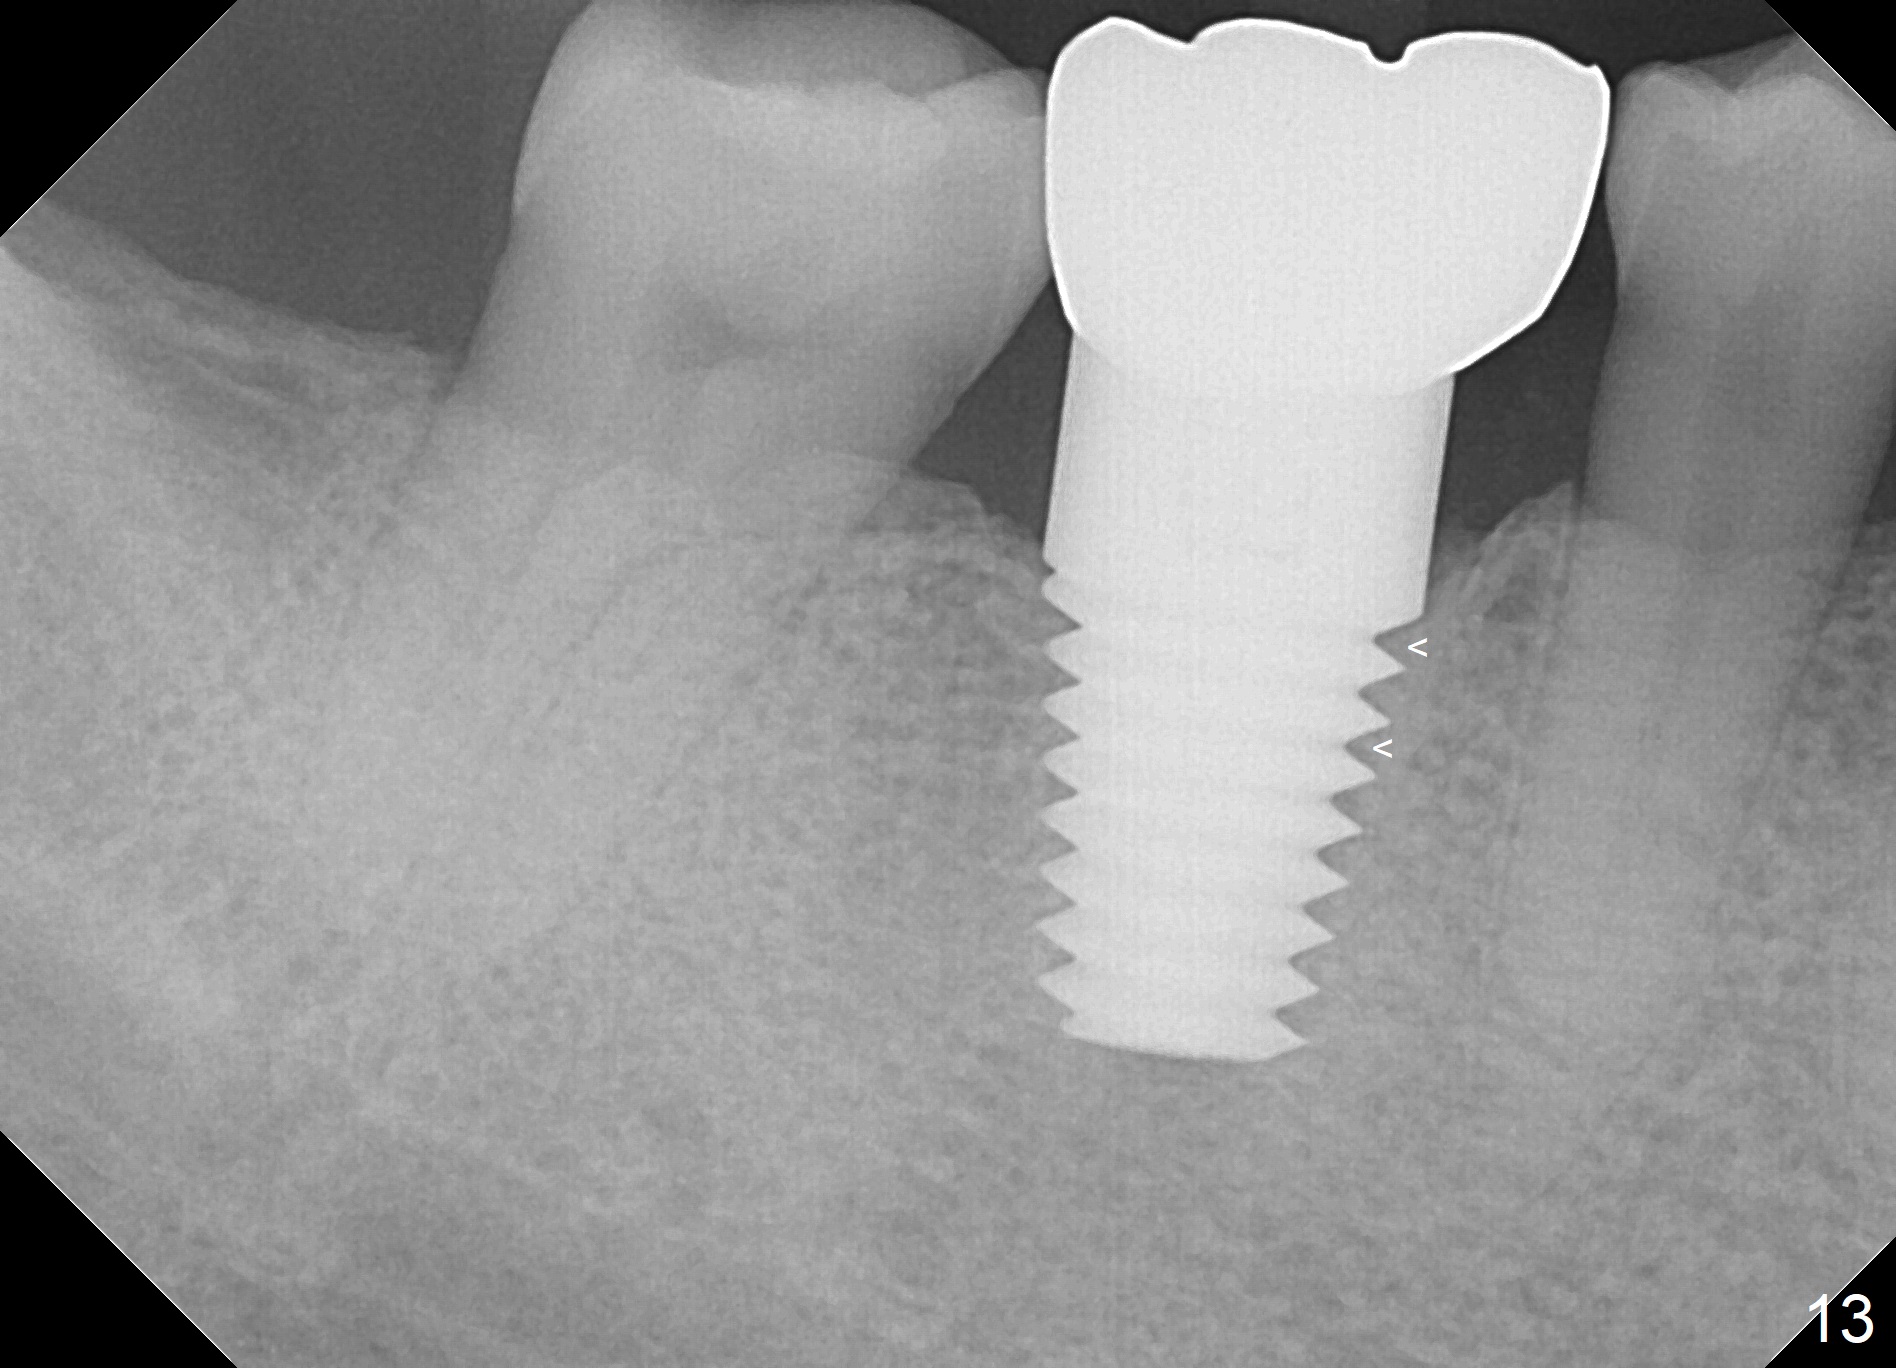

When a large implant is placed in a molar socket, one dimension of the remaining socket is small (buccolingual for lower, mesiodistal for upper). It is apparent that the mandibular buccal and lingual gingiva is relatively loose for the most time, the mesial and distal socket could be closed by suturing and perio dressing. The maxillary palatal gingiva is particularly thick and tough to be approximated. It appears necessary to develop a technique using an immediate provisional to close the socket or place an abutment. Cortex-like bone seems to have grown into the mesial thread spaces 3 years post cementation (Fig.13 <). The 7x17 mm implant was placed buccal (Fig.14 B). The slowly resorbed buccal plate seems to darken the buccal gingiva (Fig.15 B). The bone next to the implant is dense 6 years post cementation (Fig.16 *). The implant at 19 should be smaller and placed lingual.